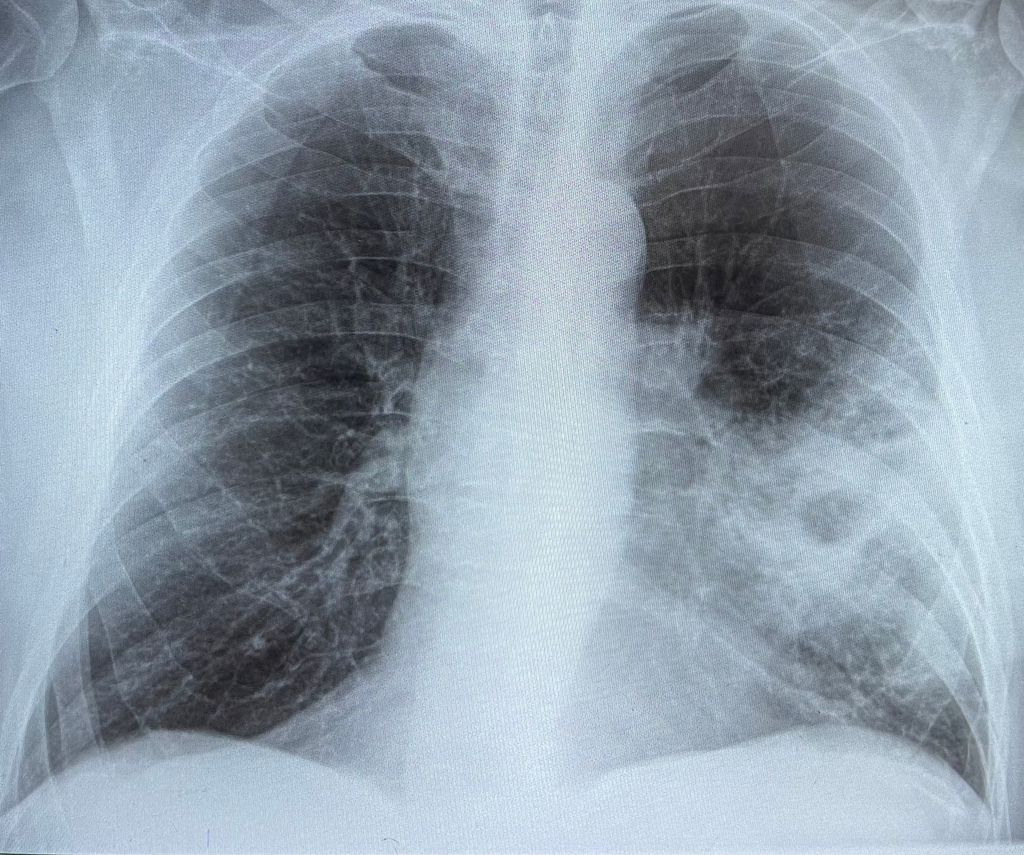

Zdravje je naša najdragocenejša vrednota, a se pogosto njegovega pomena zavemo šele, ko se pojavijo težave ali pa ko ga začnemo izgubljati. Ena izmed resnih zdravstvenih groženj, ki ogroža predvsem starejše in kronične bolnike, je bakterijska pljučnica, ki jo povzroča bakterija Streptococcus pneumoniae.

Pnevmokokne okužbe se lahko hitro razvijejo in povzročijo težke zaplete, kot so pljučnica, vnetje sinusov, sepso ali celo meningitis. Ker se bakterija prenaša s kužnimi kapljicami ob kihanju in kašljanju, se ji ni mogoče popolnoma izogniti. Lahko pa se zaščitite – z enostavnim in učinkovitim cepljenjem.

Pljučnica je resna bolezen, ki lahko povzroči dolgotrajne zaplete in celo smrt. Še posebej v zimskih in prehodnih obdobjih spomladi in jeseni, ko so naša dihala šibkejša, se tveganje za okužbe poveča. Cepljenje je ena najučinkovitejših preventivnih metod, ki lahko zmanjša tveganje za hude zaplete in zmanjša potrebo po hospitalizaciji.